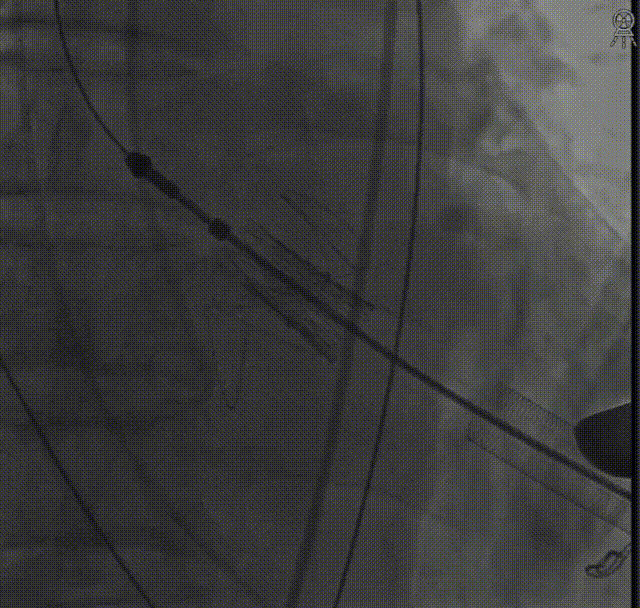

定位件入窦后造影:

降瓣至窦部:

完成瓣膜释放:

复查根部造影,未见明显反流: